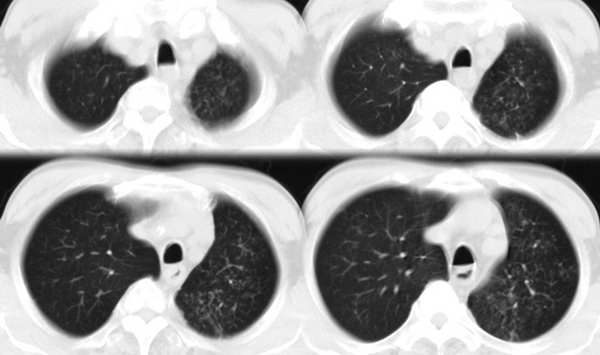

m67y外院ct诊断肺ca,现来我科复查ct

左肺下叶支气管狭窄局部见肿块影左肺下叶不张,肺癌应该没问题吧

典型中央型肺ca

左主支气管变窄,左下叶部分不张,考虑肺癌可能性大

考虑左下肺中央型肺癌并肺不张,建议支气管镜检查。

肺癌半癌性淋巴管炎。

左下肺中央型肺癌并不张可能性大,为慎重起见,请楼主提供病史,以排除支气管内膜结核引起肺不张。

左中央型肺癌并左下叶肺不张,建议纤支镜检查.

左下肺中央肺ca并下肺不张